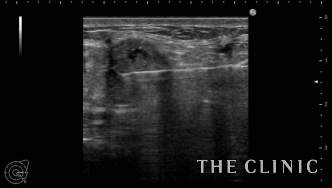

エコー検査では、両方のバストに多数のしこりを確認。超音波を反射しそれより内部が黒くなりなっていることから、しこりの辺縁には石灰化が認められます。

しこりはベイザーリポ(ベイザー脂肪吸引)の特殊な超音波で崩し、吸引針で穿刺することで除去しました。こちらの画像のように、エコーに映し出される映像を確認しながら行うことで、しこりに的確に吸引針を挿入することができます。